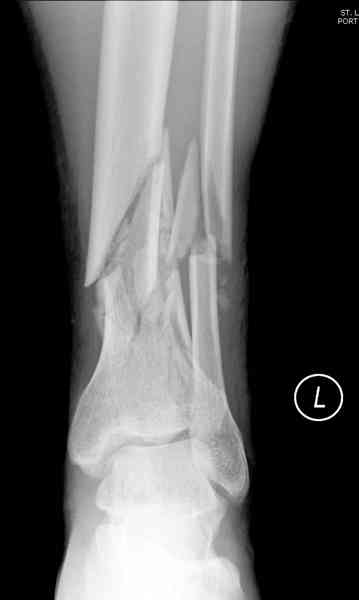

При высокоскоростных переломах редко можно встретить изолированную травму пилона, и в моей практике изолированные травмы большая редкость, поэтому, как дополнение к обсуждаемой теме, решил представить свежий, двухдневной давности случай.

Предыдущей сменой до 4:00 утра по поводу открытого перелома бедра, тибиал плато, пилон и надколенника сделана операция.

Пострадавшему 21 г., травма скоростная, после I&D с расширением раны, на бедре сделана операция ретроградным интрамедуллярным штифтом, остеосинтез с частичной резекцией надколенника и ушивание собственной связки.

КТ пилона имеем.